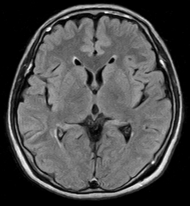

頭の病気はいったん発症すると重症となることが多いため、早期発見し早期治療することが大切です。脳ドックでは、主にMRI検査やエコー検査を用いて、症状が出るよりも先に脳と血管の変化を評価します。

脳ドックで評価できるのは、無症候性脳梗塞(かくれ脳梗塞)、未破裂脳動脈瘤、脳腫瘍、そして認知症です。MRIやエコーに加えて、血液検査、心電図、神経学的診察では、動脈硬化や脳卒中を起こしうる不整脈(心房細動)、パーキンソン病や本態性振戦の有無が評価できます。